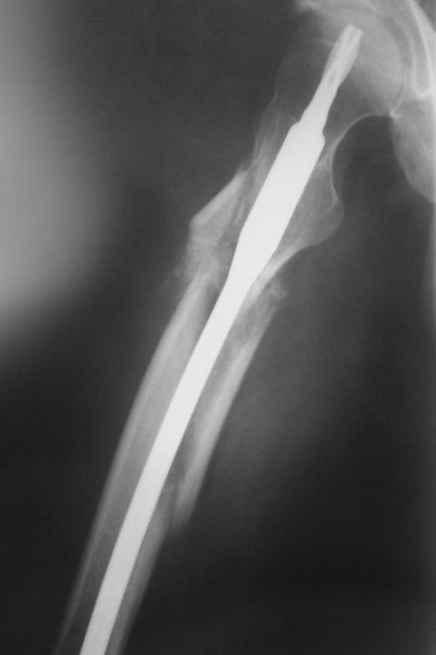

по поводу бедра - все сделано правильно, есть прекрасная апозиция основных фрагментов почти на всем диаметре перелома, в этом районе прекрасное кровоснабжение и нет никакого смысла гончяться за осколком

небольшое замечание по поводу бедра - сразу не рассмотрел - гвоздь обязательно надо было заблокировать дистально и крайне желательно -и проксимально тоже. Без блокирования не исключена ( хоть и не очень вероятна) ротация фрагментов.

Вроде ж Fixion не блокируется?

Уупс -моя ошибка, я не знал, что fixion - это expandable nail. Вопрос снят. Спасибо

Да нет, вопрос уместный. Тут перелом ниже истмуса, и в дистальном отломке винты были бы не лишние. И ретроградный Fixion с винтами есть.

Практически единственное, что делает необходимым разрез для манипуляций с промежуточным отломком бедренной кости - это его "застегивание" в илиотибиальном тракте по типу пуговицы в петле.

Когда при движениях в колене этот отломок на сантиметры смещается, создавая очевидный дискомфорт. Даже в этом случае репозиция отломка

именно в его ложе избыточна, достаточно осциллирующей пилой отсечь то, что выстоит над фасцией.

Отломок, расположенный так, как на показанных рентгенограммах бедра, обычно на снимках в 1-2 мес. уже располагается ближе к диафизу и

включается в мозоль.

На операции я оставил осколок в области приводящих мышц бедра (ни пальпаторно, ни спицей сдвинуть не смог, "заклинило" насмерть). Фото спустя 2 месяца после операции (PFN).

Только сейчас пациент стал более или менее активным. Сразу после операции жалобы на сильные боли при отведении и приведении бедра в области отломка. Сейчас отломок пальпируется и пациент испытывает дискомфорт, хотя амплитуда движений объективно прогрессирует.

Теперь думаю, надо все-таки было через минидоступ или резецировать, либо репонировать. Обычно при таких операциях уже на 2-й день пациенты на костыли и по отделению, а у этого задержка длительная получилась. Только спустя 2 недели кое-как на костыли взобрался. Ни отека, никакой неврологии, только эти боли в области осколка.